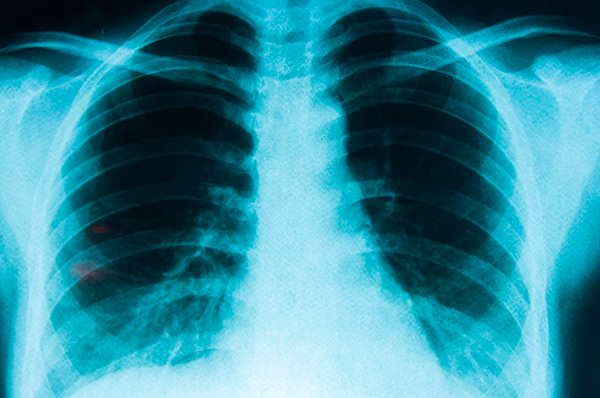

Se trata de la patología oncológica con las tasas más altas de mortalidad, siendo el tabaco y la contaminación sus principales factores de riesgo.

El 17 de noviembre se conmemoró el Día Mundial del Cáncer de Pulmón, una fecha que busca concientizar sobre la principal causa de muerte oncológica en Chile y el mundo. Según datos del Departamento de Estadísticas e Información de Salud (DEIS) del Minsal, 3.511 personas perdieron la vida por cáncer de pulmón en nuestro país durante el año 2023, casi un 1% más en comparación con el 2022.

La realidad chilena es alarmante: 10 personas fallecen al día por esta enfermedad, cuyo principal factor de riesgo es el tabaquismo. “8 de cada 10 muertes por cáncer de pulmón están asociados al consumo de tabaco y 9 de cada 10 personas con cáncer de pulmón fuman”, asegura el Dr. Juan Emilio Cheyre, jefe del equipo de Cirugía de Tórax de Fundación Arturo López Pérez (FALP).